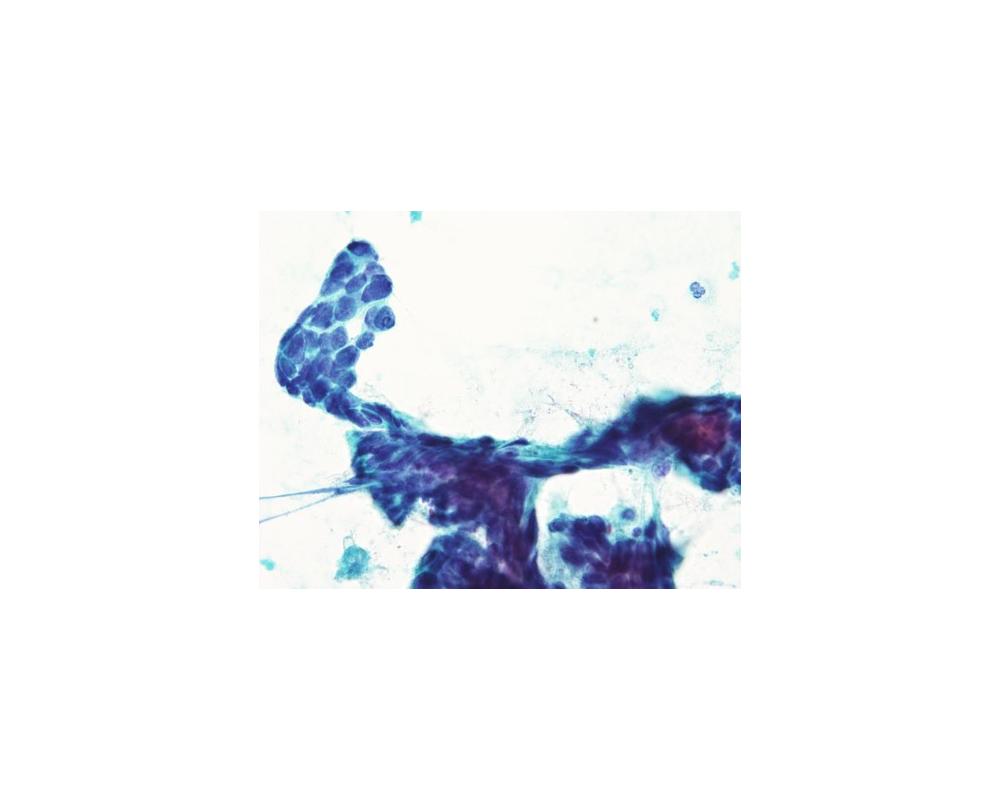

第40回日本臨床細胞学会九州連合会学会(大分)スライドカンファレンス症例4

種別:甲状腺

出題:松岡 優毅1、中島 正洋1,2 1長崎大学病院 病理診断科・病理部、2長崎大学原爆後障害医療研究所 腫瘍・診断病理学研究分野

| 年齢 | 80代 | 性別 | 女性 |

| 採取部位 | 甲状腺 | 採取方法 | 穿刺吸引細胞診 |

| 検体処理法 | ふきつけ |

既往歴・家族歴: なし

現病歴: 3か月前に7cm大の嚢胞性病変が指摘され穿刺吸引細胞診(Class III).増大、嗄声が確認され、再度穿刺吸引細胞診が施行された。なお、CT上では甲状腺から外方向性発育を示していた。採血データはThyroglobulinが84.3ng/mL(正常35.0以下)で、TSH、free T4、抗Tg抗体、抗TPO抗体は正常範囲内であった。

| 正解 | 4.Teratocarcinosarcoma |

▼選択肢及び投票結果

| 1.Adenomatous goiter | 10件 | (9.5%) | |

| 2.Papillary carcinoma | 27件 | (25.7%) | |

| 3.Intrathyroid thymic carcinoma | 48件 | (45.7%) | |

| 4.Teratocarcinosarcoma | 15件 | (14.3%) | |

| 5.Follicular neoplasm | 5件 | (4.8%) | |

| 投票総数 | 105件 | (100%) |